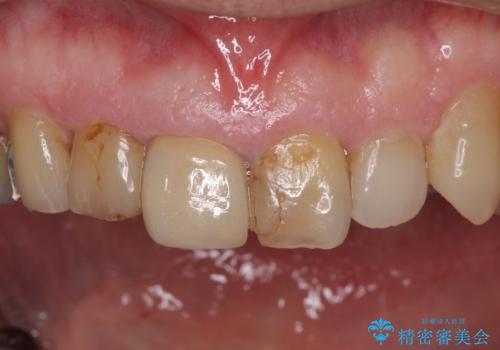

- 前歯がぐらつくことを主訴にご来院された患者様です。ご本人は抜歯と考えており、インプラント以外の治療をご希望でした。しかしながらぐらついていた原因は、古い差し歯が取れかけていたことでした。

遠方から通院されること、仕事上短期間で治療したいとのことを考慮して、残っている歯はかなり小さいものの、保存すべきと判断して当日処置から行いました。

西日本から新幹線でご来院された患者様です。前歯は都内の医院でやりたいとのことで、はるばる通院してくださいました。通院回数が最小限になるよう工夫しました(1回あたりの時間は長くなります)。

残っている歯が小さいと、差し歯はぐらつきやすくなりますが、その形態によっては抜歯を回避できることがあります。